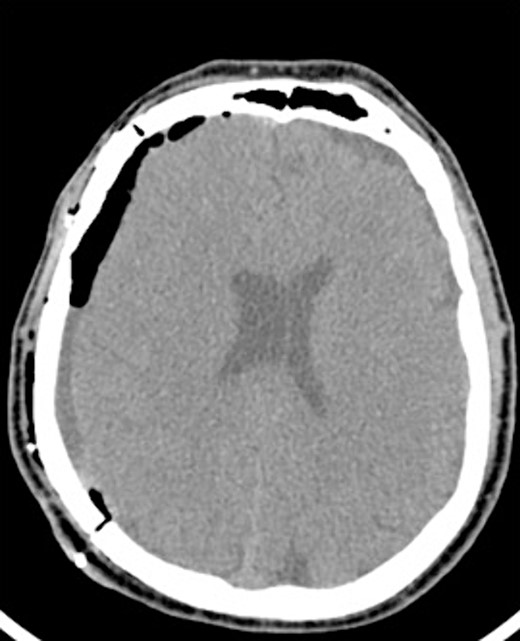

After the head was positioned in a supine neutral position on a horseshoe head holder, the AR system was used to overlay the hematoma and other relevant anatomy onto the patient’s head. Midline locations, vasculature and the blood collection were appreciated via AR overlay prior to marking an incision (Fig. 5). The AR overlay was then used to plan two separate linear incisions for two right-sided burr holes—one frontal and one parietal over the largest components of the hematoma as visualized with AR. A perforator drill was used to create the two burr holes which were widened with a burr and rongeurs. Beneath the dura, a hematoma was identified and its thick membrane layer was coagulated with bipolar cautery. The surgical sites were irrigated with saline to evacuate chronic blood. A ventriculostomy catheter was then placed into the subdural space at the frontal burr hole and tunneled lateral to the incisions. The burr holes were covered with titanium covers. There were no intraoperative complications, and the tolerated procedure well with improved cognitive function several days after surgery. Post-operative CT demonstrated significant interval decrease in hematoma volume and reduction in midline shift (Fig. 6).